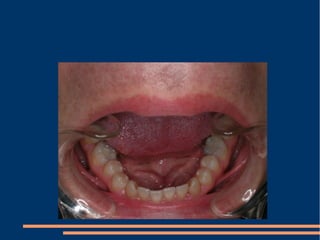

!!! A simple aesthetic treatment PPT